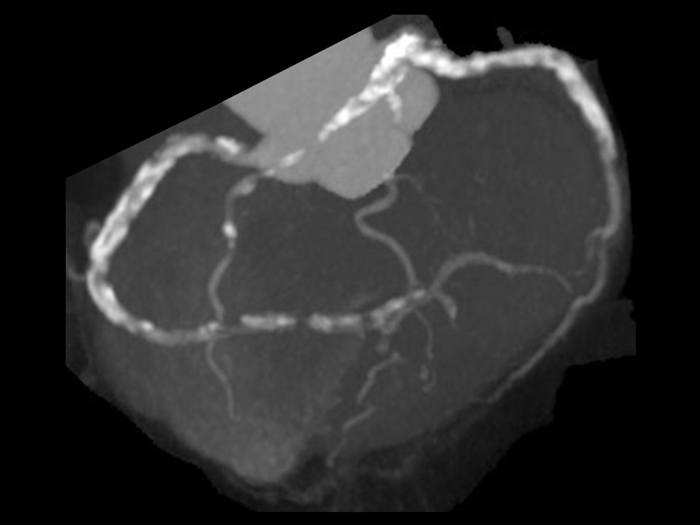

息止め不良

息止め不良による階段状アーチファクト(64列CTによる撮影)

撮影時の息止め不良も大きなアーチファクトの原因となります。

特に64列CTでは5心拍程度の時間で撮影しますので、このようなアーチファクトが出やすくなります。

意識レベルの低い患者さん、認知症患者さん、心臓や肺の疾患で呼吸状態が悪い患者さんでは、

息止めが不十分になりやすいので注意しましょう。